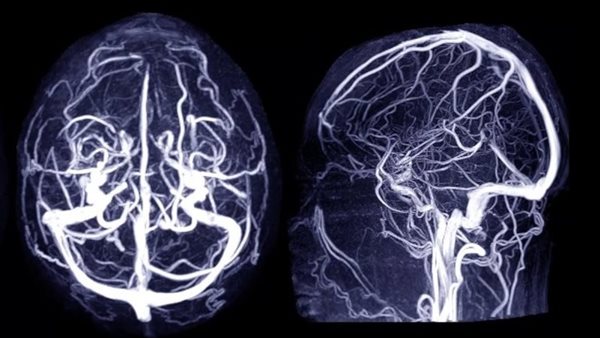

خطر تمدد الأوعية، هو انتفاخ أو تضخم في أحد الأوعية الدموية في الدماغ. وغالبًا تتخذ حالة أم الدم شكل ثمرة توت متدلية من غصن.

خطر تمدد الأوعية تتشكل وتنمو بسبب ضغط الدم المتدفق عبر الأوعية الدموية على منطقة ضعيفة من جدار الوعاء، وتزيد هذه الحالة من حجم أم الدم في الدماغ، إذا تعرضت أم الدم في الدماغ للتسرب أو التمزّق، فقد تسبب نزيفًا في الدماغ، وهو ما يُعرف بالسكتة الدماغية النزفية.

ويحدث خطر تمدد الأوعية في الدماغ غالبًا في الفراغ الواقع بين الدماغ والأنسجة الرقيقة المغطية له، ويُطلق على هذا النوع من السكتات الدماغية النزفية اسم النزيف تحت العنكبوتية.